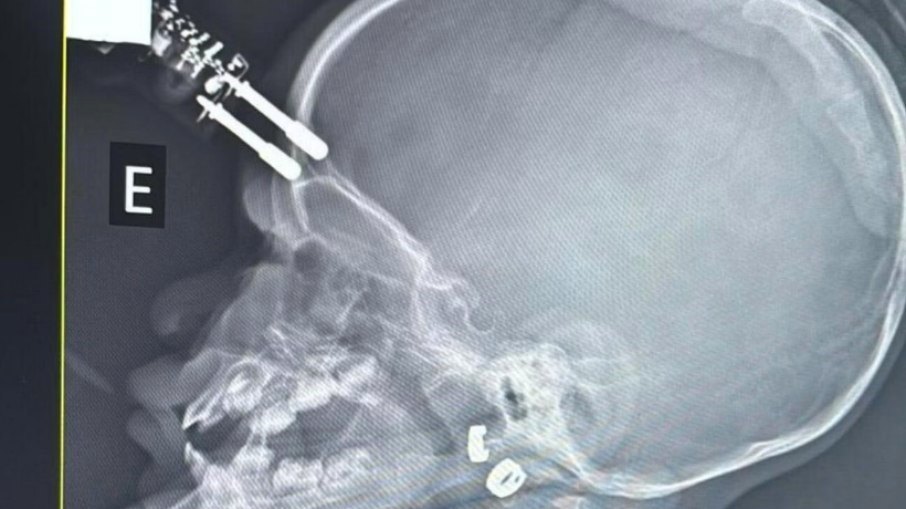

Exames de imagem apontaram que o objeto atravessou o crânio, o que levou a equipe médica a encaminhar a menina imediatamente para o bloco cirúrgico

Exames de imagem apontaram que o objeto atravessou o crânio, o que levou a equipe médica a encaminhar a menina imediatamente para o bloco cirúrgico. O procedimento foi realizado para a retirada segura do corpo estranho e para evitar complicações neurológicas. Após a cirurgia, a criança permaneceu 36 horas no Centro de Terapia Intensiva (CTI) e, na sequência, recebeu alta médica, sem sinais aparentes de sequelas.